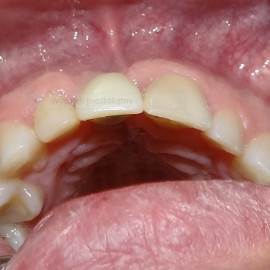

Korona protetyczna na implancie, funkcjonująca od roku 2003. Zdarzył się wypadek motocyklowy. Widzimy klucz do osiągnięcia sukcesu: mikrochirurgia i poprawna anatomiczna odbudowa tkanek. Tego nie zastąpi nawet najdroższy implant!